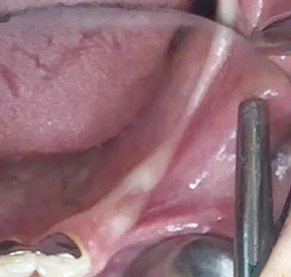

Partial edentulous clinical cases